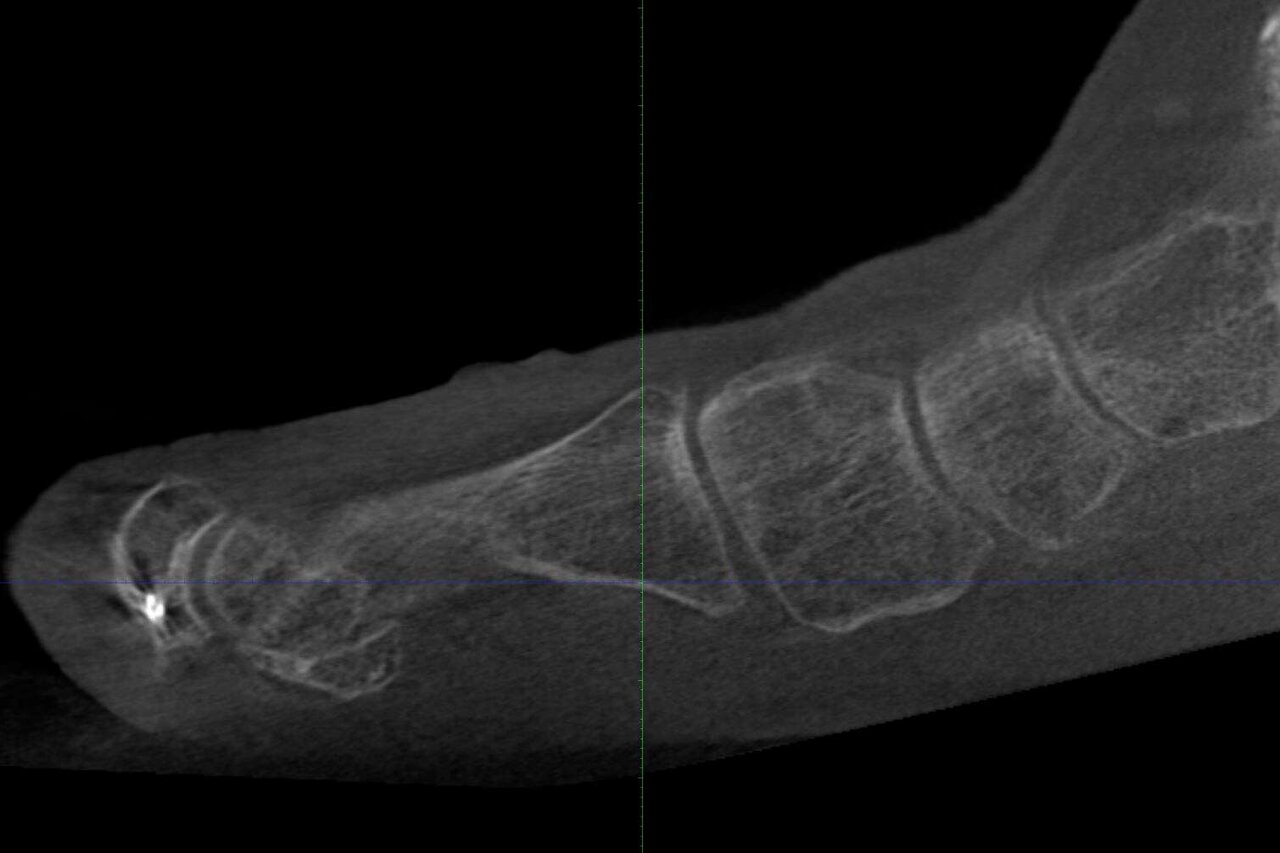

Home Schwerpunkte Krankheitsbilder Hallux Valgus – die krumme Großzehe richtig behandeln schwere TMT 1 Instbilität

schwere TMT 1 Instbilität